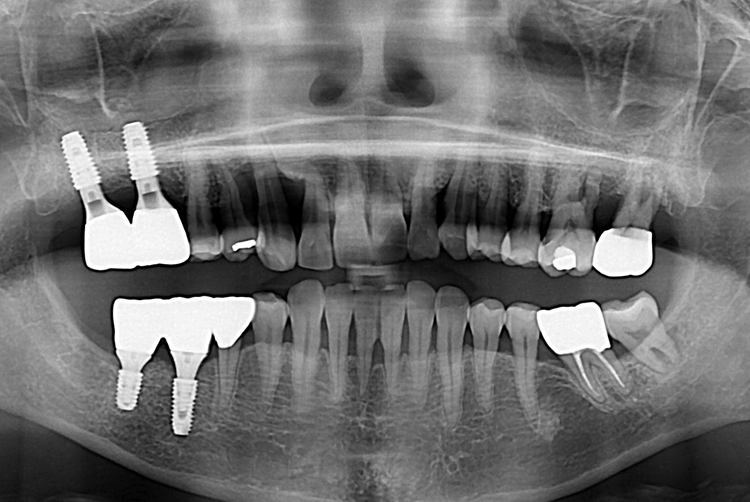

[임플란트] 어금니 임플란트

치료후 : 2019-06-12

세종치과는 많은 환자와 다양한 케이스를 바탕으로

항상 편안한 임플란트 수술을 제공하고자 노력하고,

오래동안 튼튼히 쓸 수 있는 임플란트 수술을 가장 큰 목표로 삼고 있습니다.